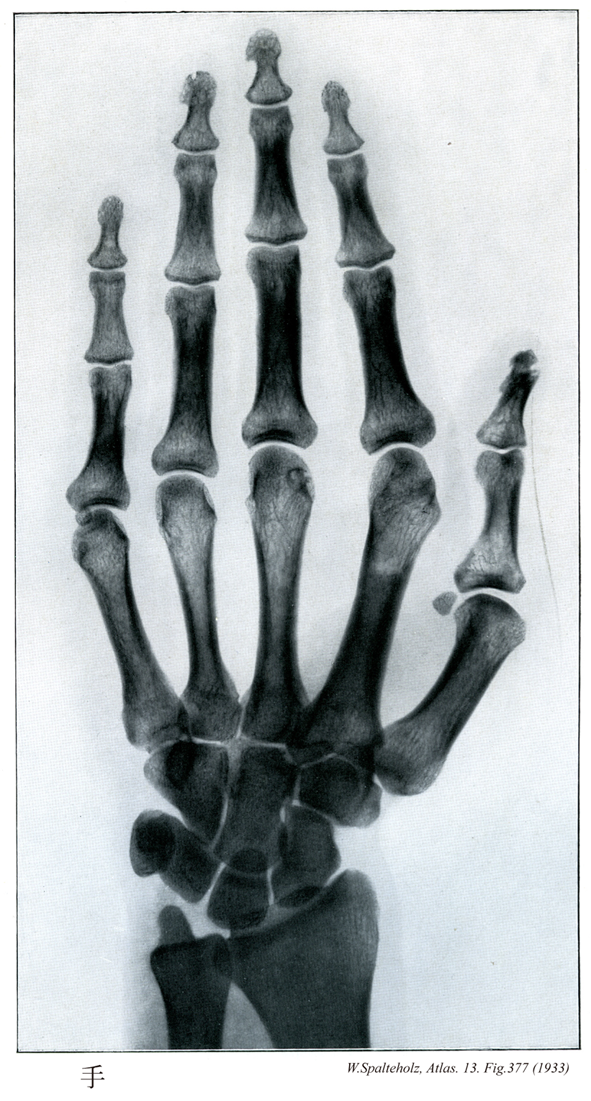

377

【Hand

手;テ

Manus】

→(手は上肢のうち橈骨手根関節より遠位の部分。手根と中手に区別され、手根と中手の前面を手掌、後面を手背という。皮膚節において第六頚神経、第七頚神経、第八頚神経のレベル。)